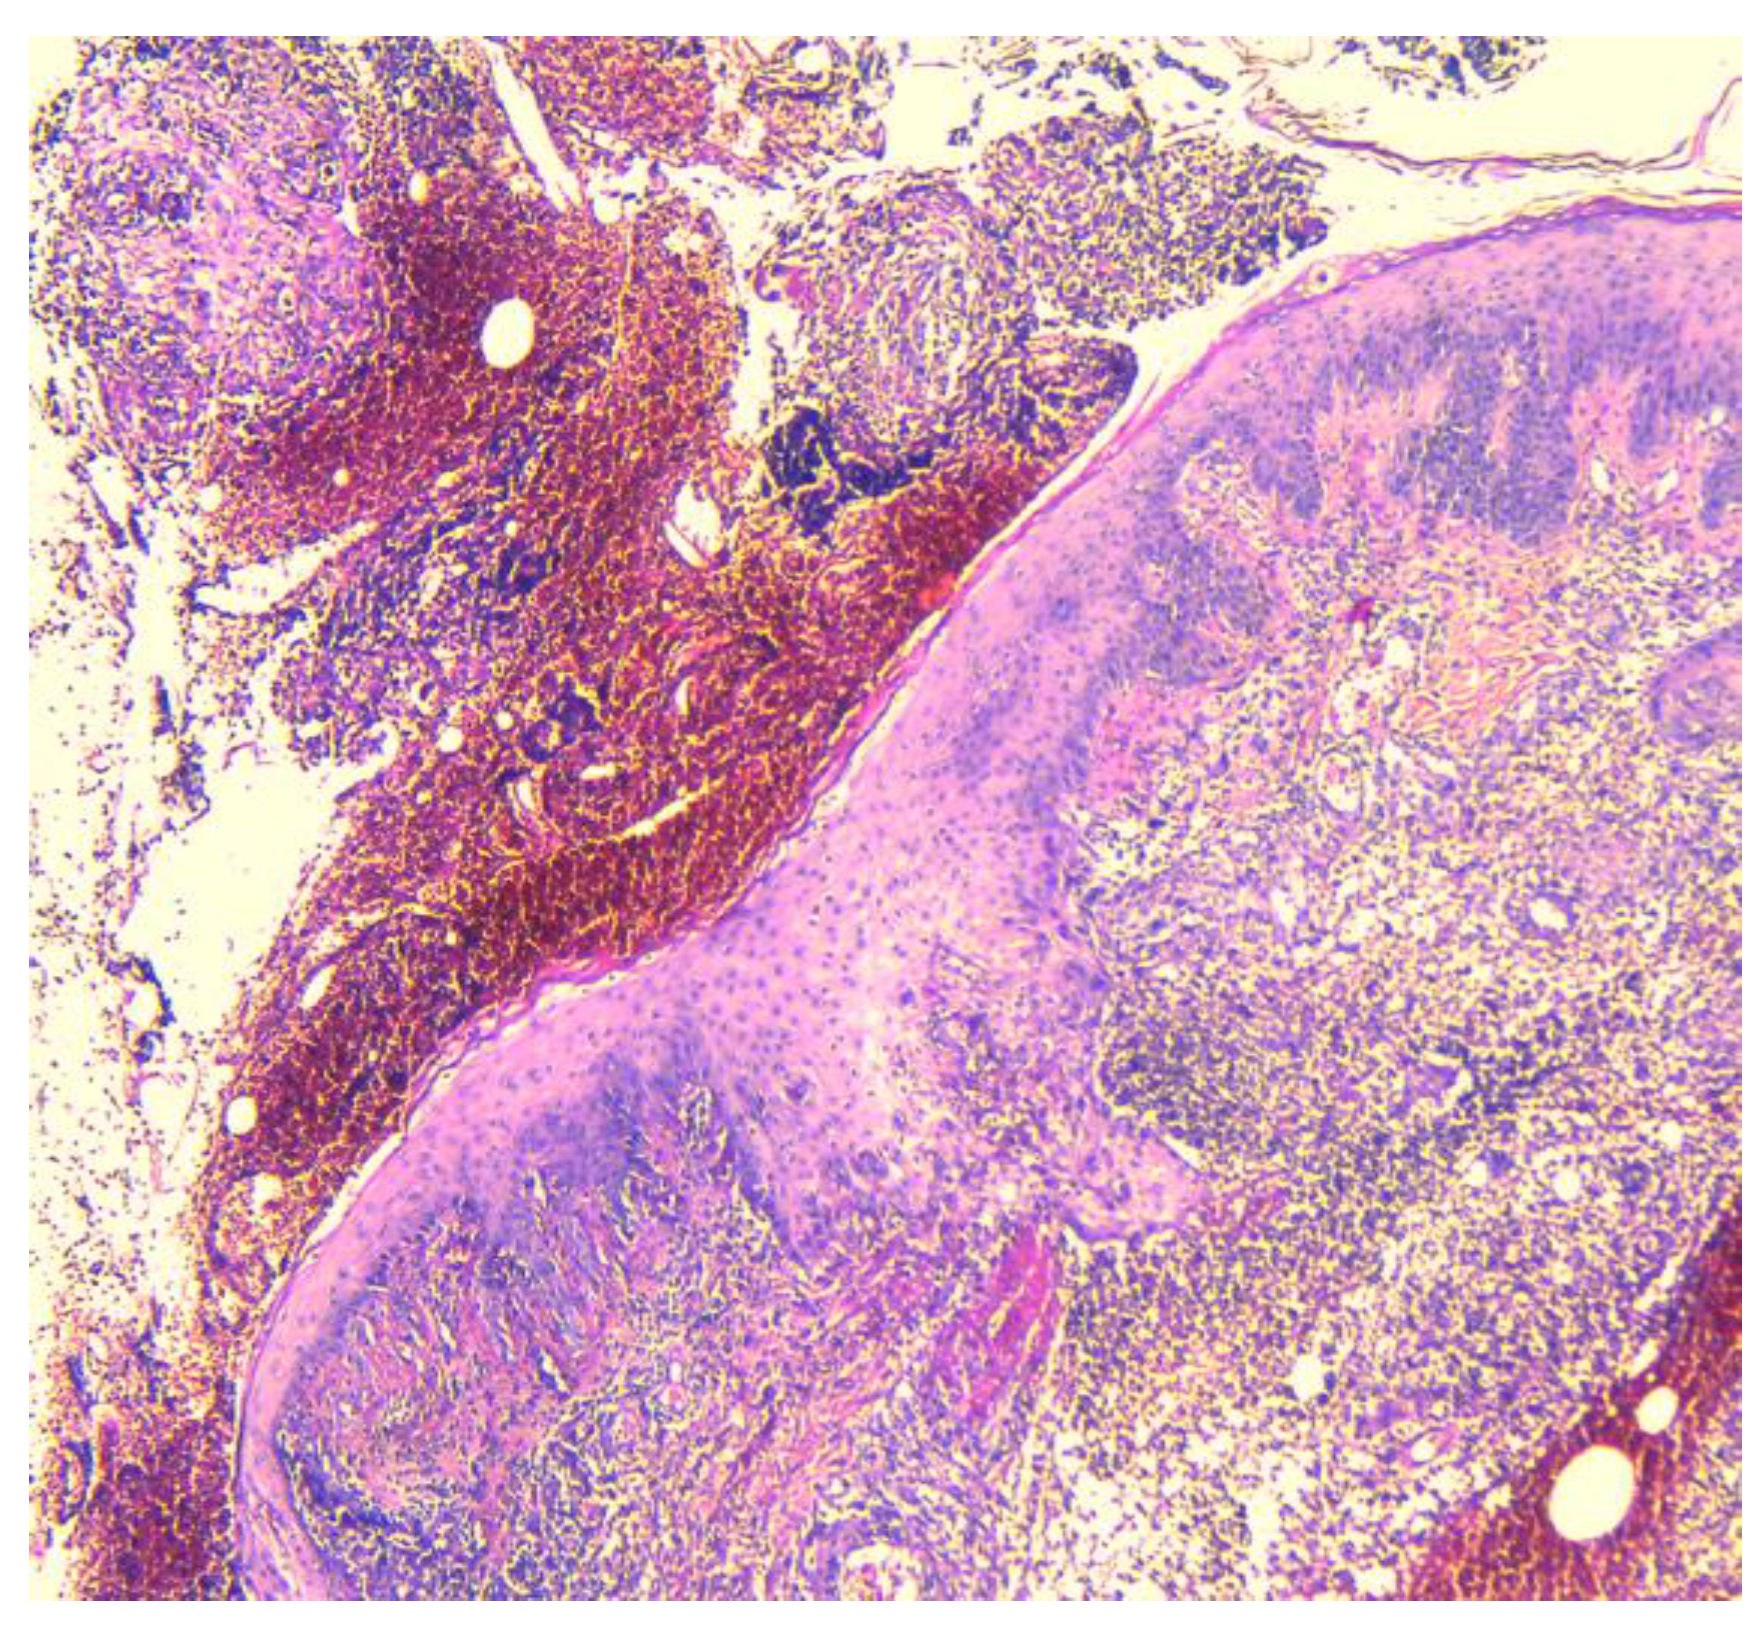

2.2. Histopathology Findings